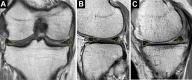

Methods: Included were 36 knees that underwent OWHTO from March 2014 to February 2016 and had postoperative serial MRI. The MRI was performed at 19.9 ± 7.4 and 52.3 ± 8.3 months postoperatively, and the cartilage and meniscal changes were evaluated by highlighting the regions of interest. We evaluated the T2 relaxation times of each cartilage and meniscal area, the cross-sectional area of the menisci, and the extrusion of the medial meniscus (MM). The meniscochondral unit was assessed using subgroup analyses according to the status of the MM.

Results: Significant decreases were seen in T2 relaxation times in the medial femoral condyle (MFC) (P < .001) and medial tibial plateau (MTP) (P = .050), and significant increases were seen in the lateral femoral condyle (LFC) (P = .036). The change was more prominent in the MFC compared with the MTP and LFC (P = .003). No significant changes were observed in the lateral tibial plateau, patella, or trochlear groove. The area of the lateral meniscus (body and posterior horn) was decreased compared with preoperative MRI (P < .001 for both). The extent of MM extrusion decreased between the preoperative, first follow-up, and second follow-up MRIs (P < .001).